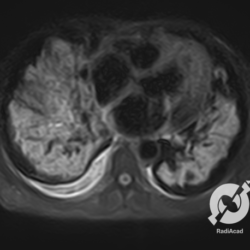

Lesões intersticiais reticulares difusas, cardiomegalia, derrame pleural á direita (Rx)/Opacidades em vidro fosco, cardiomegalia e aumento do calibre das estruturas venosas.